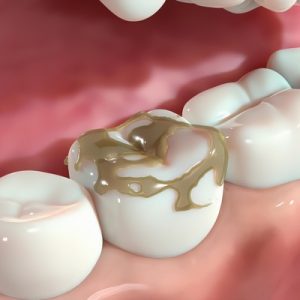

When the cavity-causing bacteria (from sugars and starches) or highly…